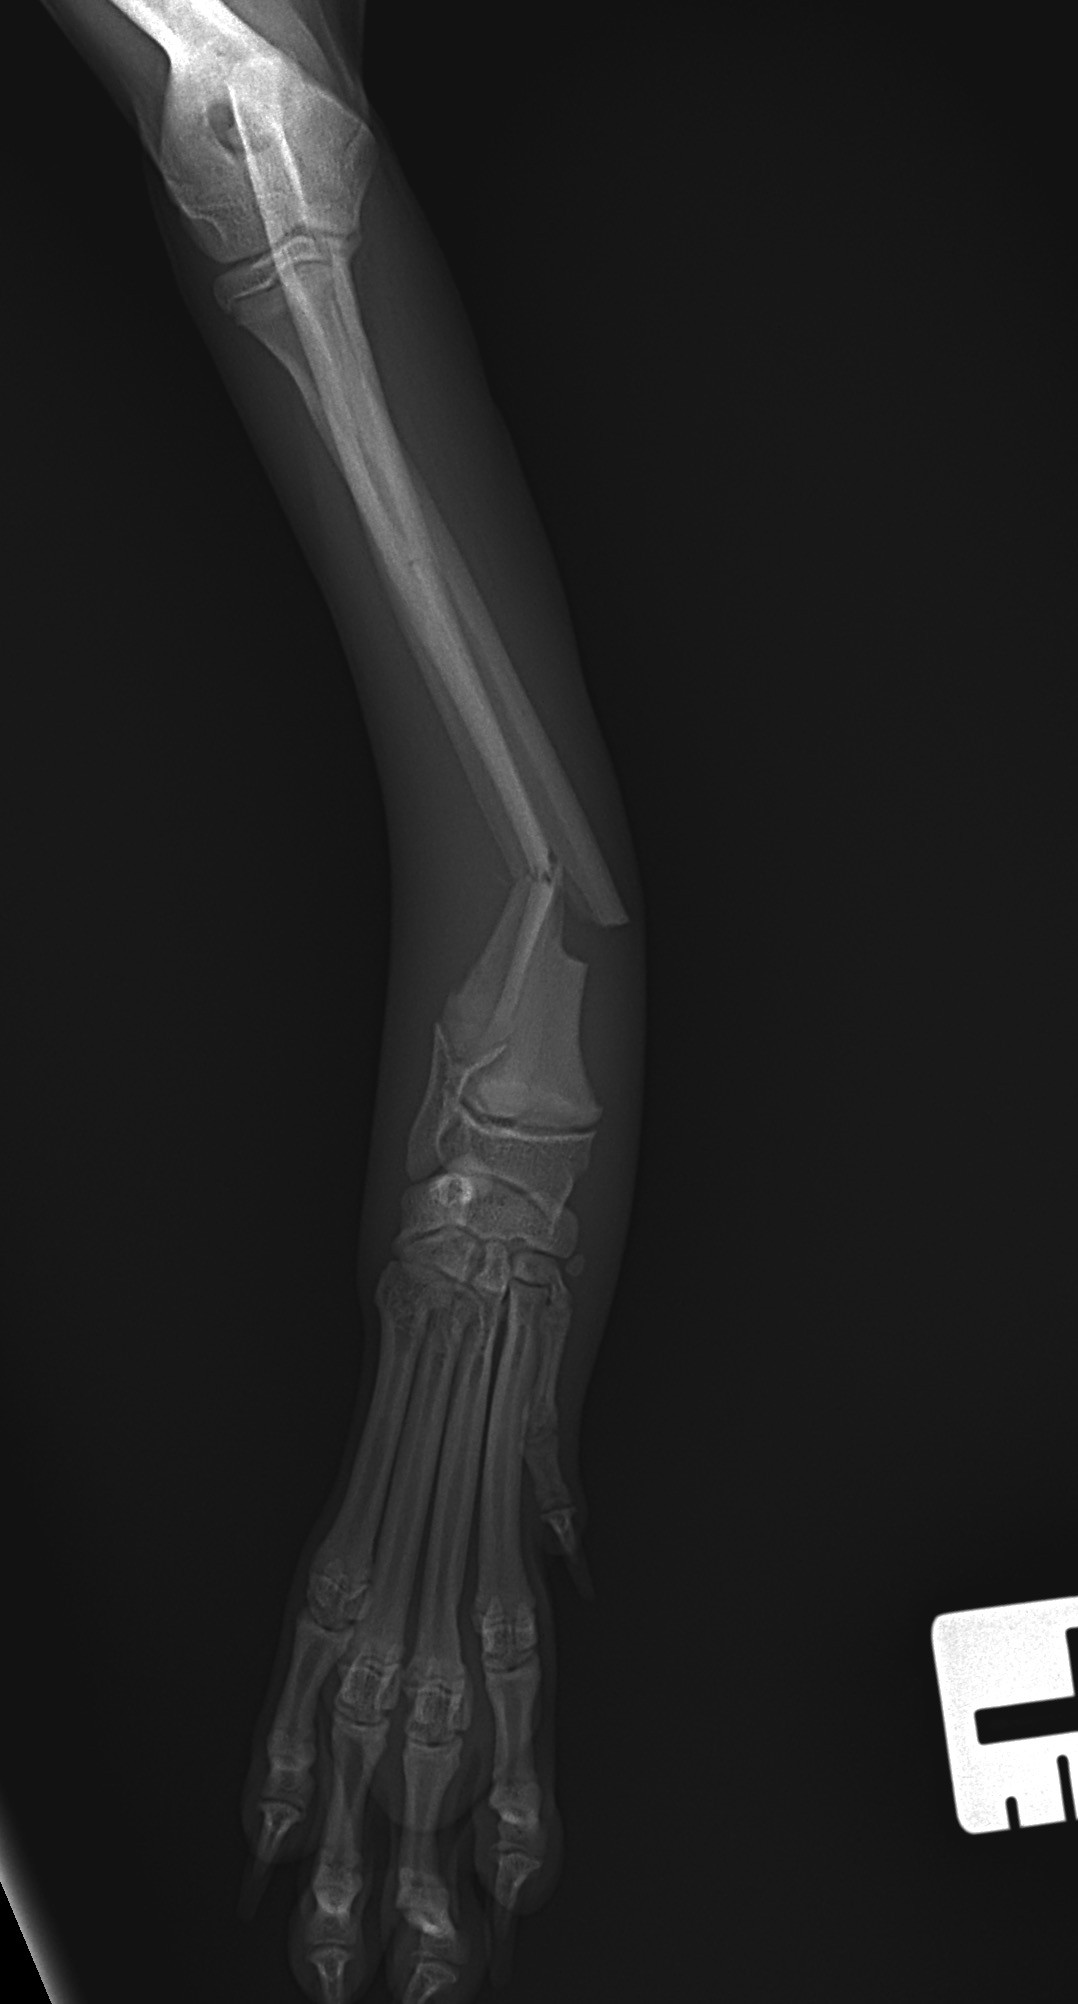

5ヶ月齢の小型犬がソファーからジャンプしたのちに橈骨骨折をしたとの事で、かかりつけ医より紹介受診されました。橈骨は遠位で階段状斜骨折を呈していました。遠位3穴にデザインされたストレートの1.5 Locking Plateをメインとし、橈骨の内側面からOrthogonal Plateにより骨接合術を行いました。しばらくは安静が必要です。